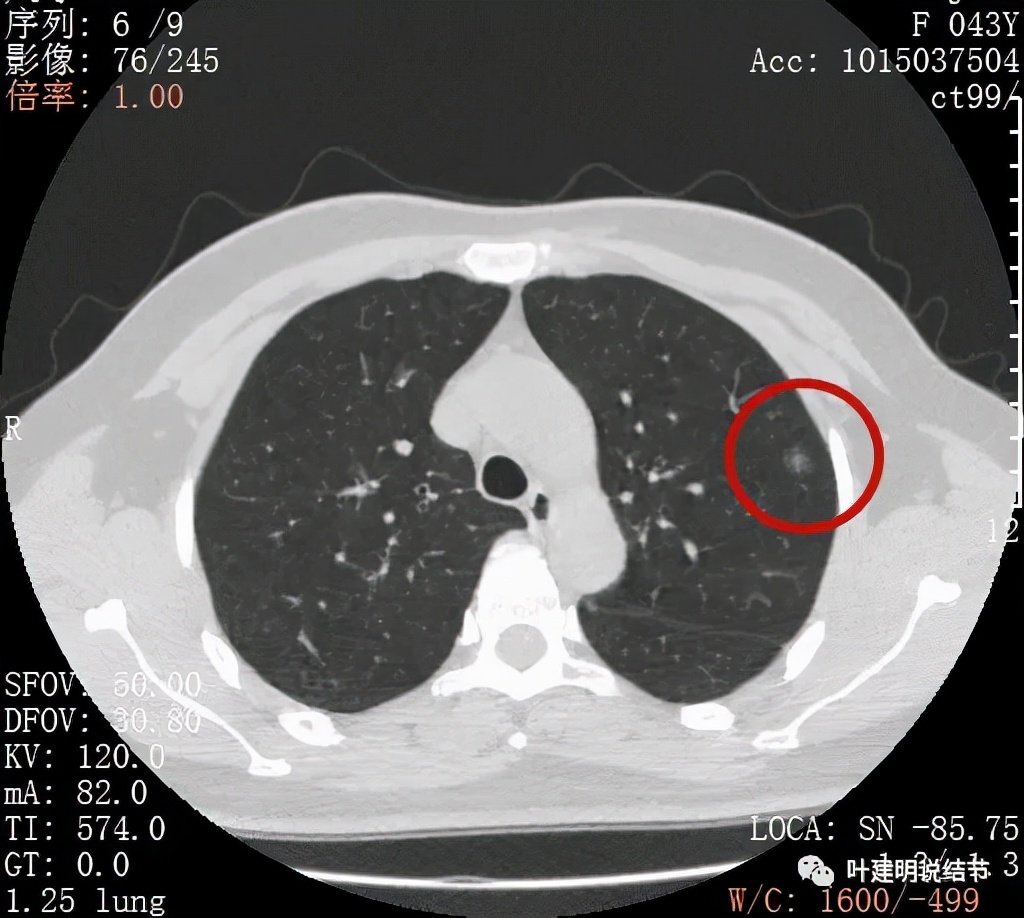

从以上靶扫描图像上看,给人的印象是肿瘤范畴的结节,是混合磨玻璃结节,但磨玻璃部分的密度偏低,有的边缘显模糊,中间有点状高密度,也有微小血管进入,应该至少微浸润性腺癌可能性大。持续存在已经2月余,位置又还靠边上的,可考虑手术切除。下面再来瞧瞧后处理重建的图像:

上图非常不舒服,病灶边缘有毛刺(蓝色箭头),中间有偏实性成分(粉色箭头所指),整体看密度不均杂乱

上图示明显的血管进入(桔色箭头),而且进入病灶后散大模糊,不是穿行;病灶内有高密度区域(粉色箭头)。但事后分析,绿色箭头所指的磨玻璃部分密度仍是过低,且边缘显模糊,与浸润性腺癌可能不是太符合。

以上三图均示典型的混合磨玻璃,实性成分杂乱,整体密度杂乱,并有血管征,是较为典型的浸润性腺癌影像表现。

看了后处理重建的图像,我们认为基本上应该就是浸润性腺癌了,从平扫到靶扫到靶扫描后处理,一步一步往更恶性的角度考虑。某A按我们的建议进行了单孔胸腔镜下手术,结果术中快速病理切片示:原位腺癌。我还觉得术后病理会不会升级,所以还在等石蜡切片,因为影像上,特别是后处理重建的图像太像浸润性腺癌了,结果仍是原位腺癌: